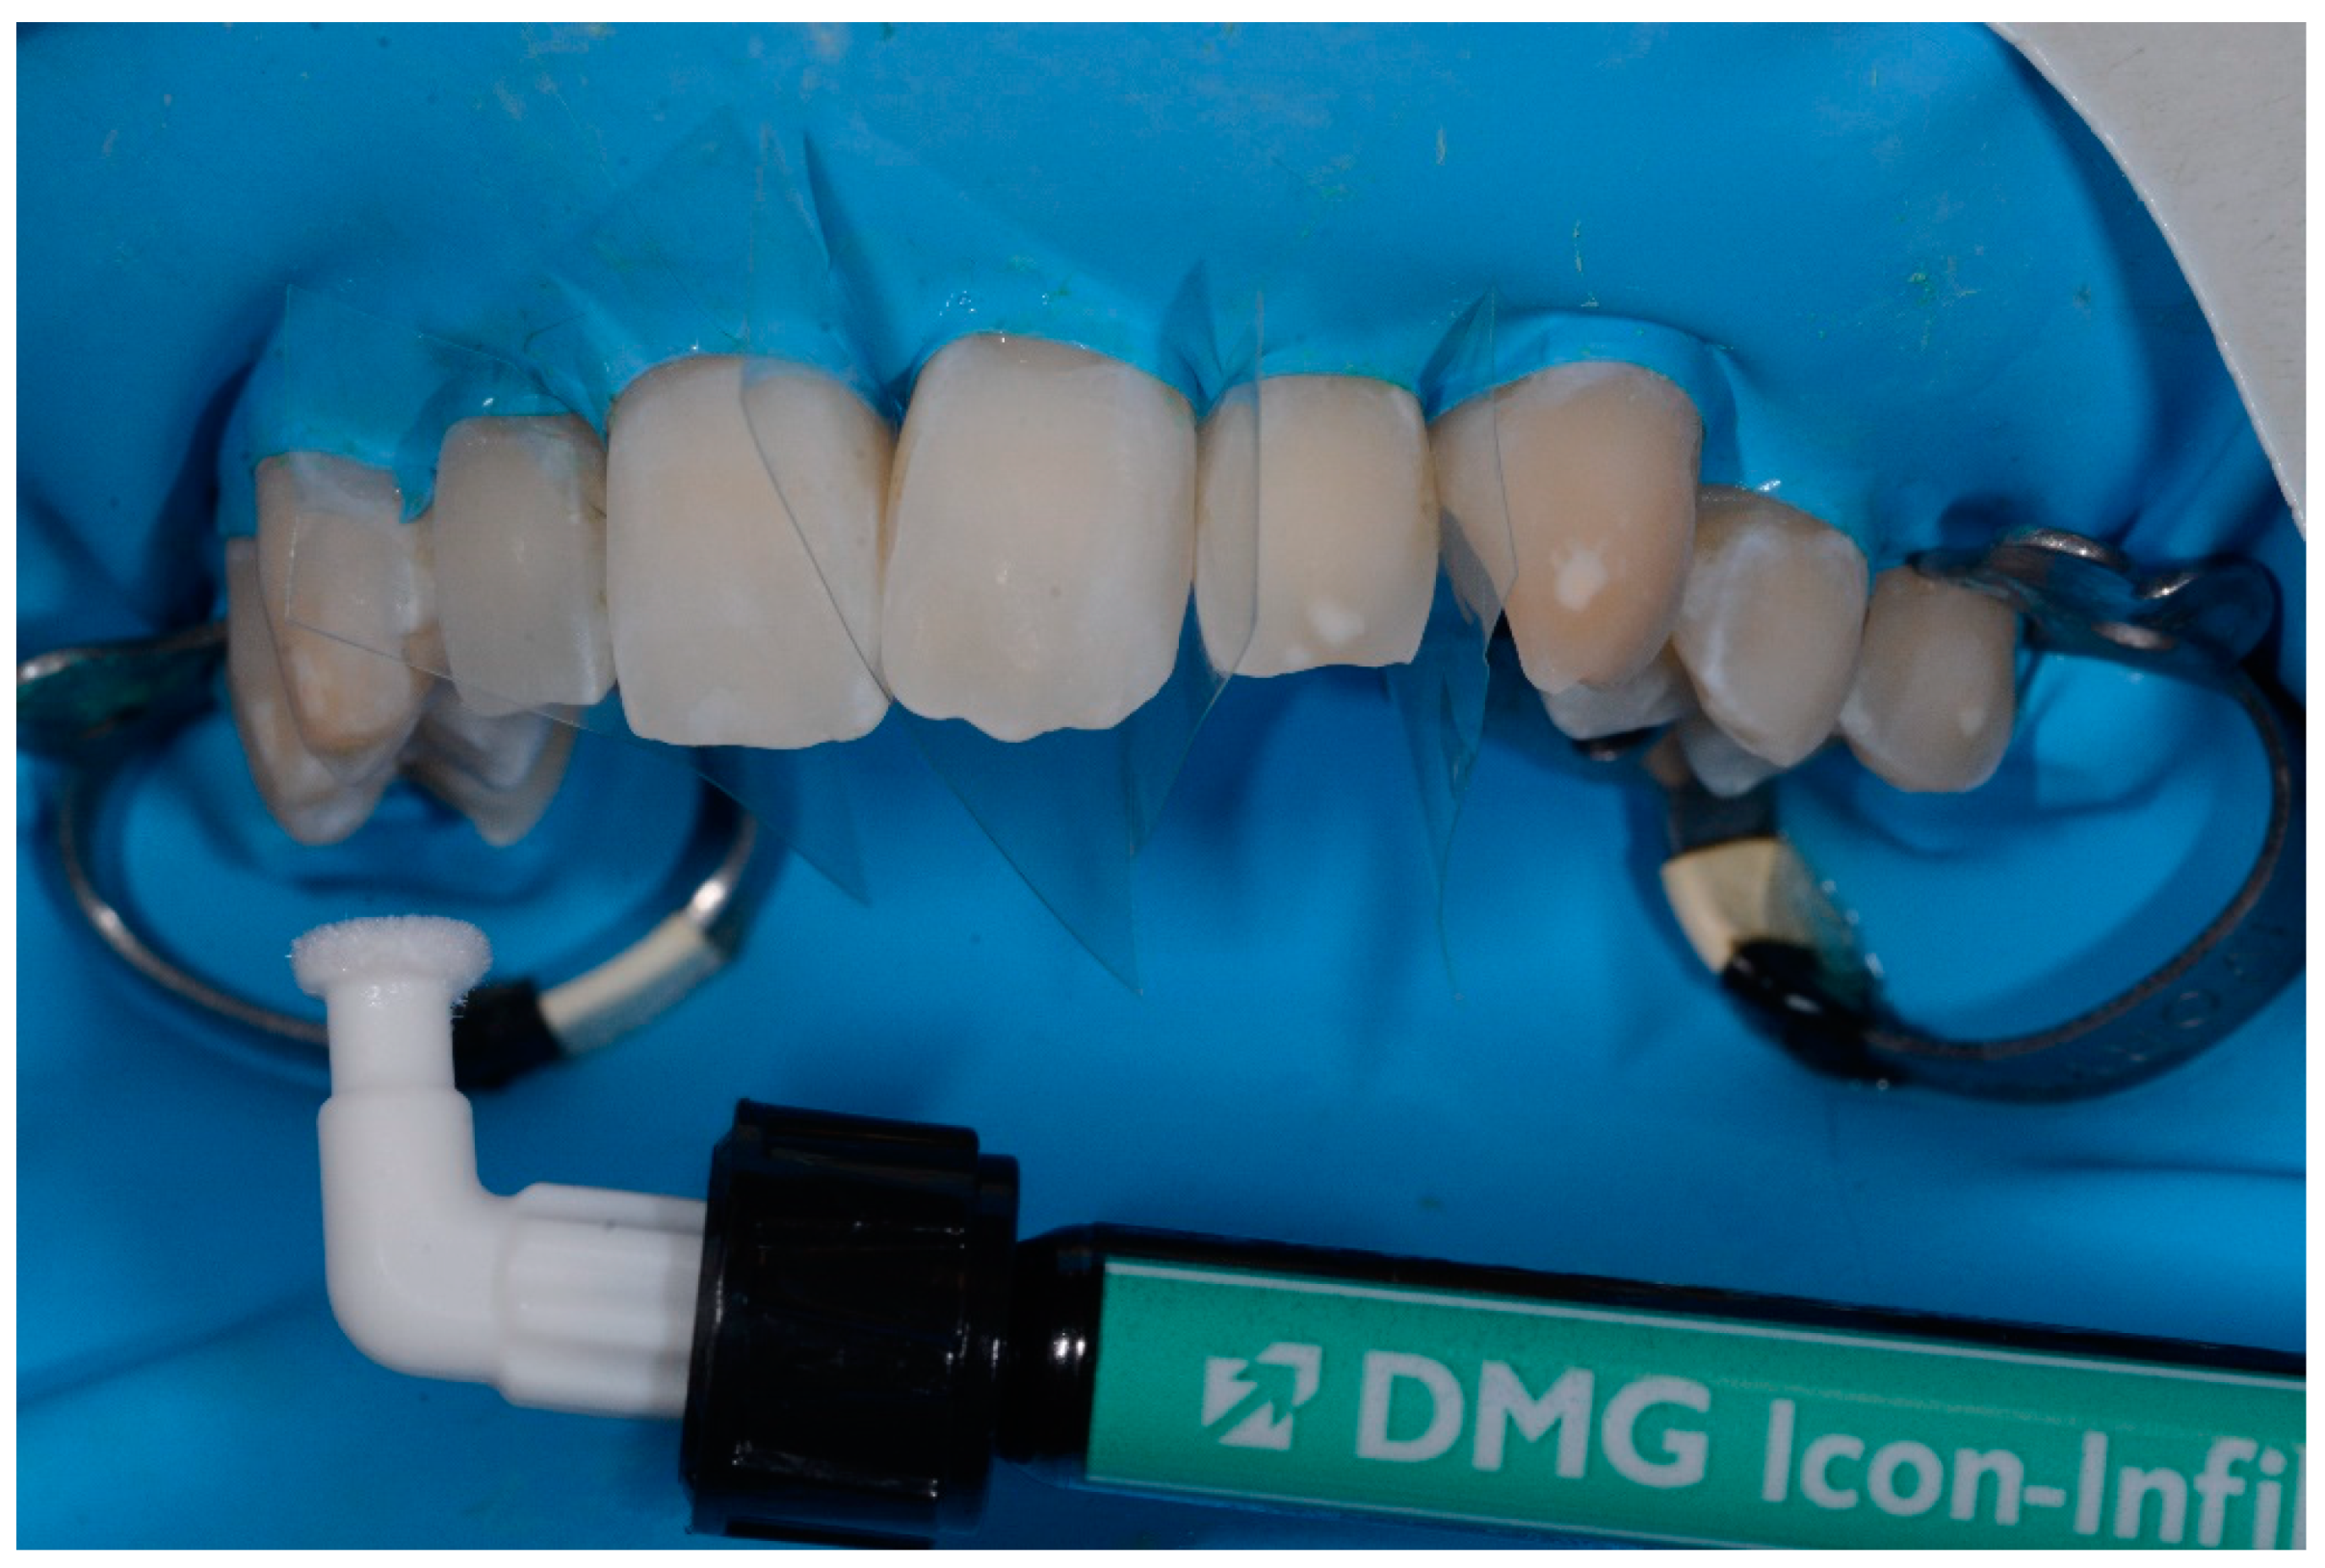

- application of 99% pure ethanol (Icon-Dry, DMG) for 30 s; (Figure 1)

- completed the drying of surfaces, application of infiltrating resin (Icon Infiltrant; DMG) left in position for 3 min; (Figure 2)